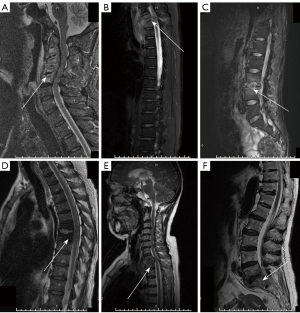

In fluid-sensitive sequences, involvement of posterior elements did not differ among the four groups. However, several other parameters were significantly different across the groups: vertebral body signal on T2WI (Infected vertebrae/normal vertebrae on T2WI), extent of vertebral destruction, presence of skip lesions, and endplate inflammatory reaction line (Figure 2). The degree of disc destruction also varied among the groups. The FS group exhibited significantly lower vertebral body signal intensity on T2WI images compared to the other groups (Figure 2). The incidence of severe vertebral body destruction was notably lower in the BS group compared to the TS and FS groups. The BS group was also more likely to have skip lesions than the PS group, although the incidence of skip lesions did not differ significantly between the TS and BS groups (Figure 3). Additionally, the FS group had a much higher incidence of endplate inflammatory reaction line compared to the other groups, while the PS group showed a higher incidence of this feature than the TS and BS groups (Table 4).

Among the parameters observed in the fluid-sensitive sequence, the slight destruction of the vertebral body in the BS group may be attributed to Brucella’s ability to activate and impede the maturation of dendritic cells, as suggested in previous studies (41,42,55). The finding of lesser disc destruction in the TS group compared to the PS group has been reported and explained in several studies, which attribute this to the absence of protein hydrolases in Mycobacterium tuberculosis (47,49). However, our results showed that posterior element involvement was not uniquely present in TS, and this feature did not differ significantly between the four groups. This is a surprising finding, as it contradicts established reports and studies that have noted differences between PS and TS with respect to posterior element involvement (17-19). Our findings suggest that posterior element involvement is not unique to TS and reflects the comprehensive nature of the present study. Additionally, this study for the first time reported the phenomenon that FS patients are prone to low signal intensity on T2WI. This could be related to the paramagnetism of the fungus, which leads to localized iron deposition and results in diffuse low signal on T2WI (55,56). In contrast to Li et al.’s study, we did observe an endplate inflammatory reaction line in the PS group, but the incidence was not as high as the 46% reported in their study (1). Interestingly, a similar phenomenon was observed in the FS group in our study, with a much higher incidence of 71%, compared to the PS group. The occurrence of this high signal may be related to the distribution of arterial blood supply to the vertebral body, although the exact cause remains unclear (55).